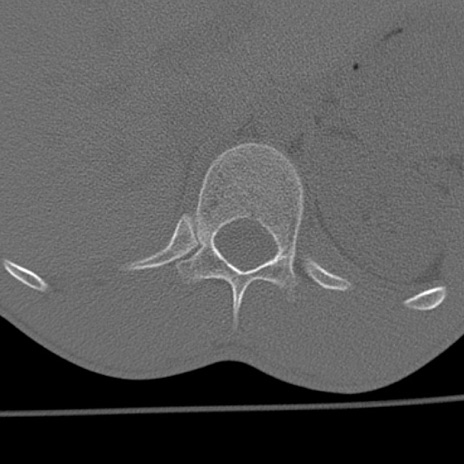

症例3 腰椎CT(横断像)

腰椎CT